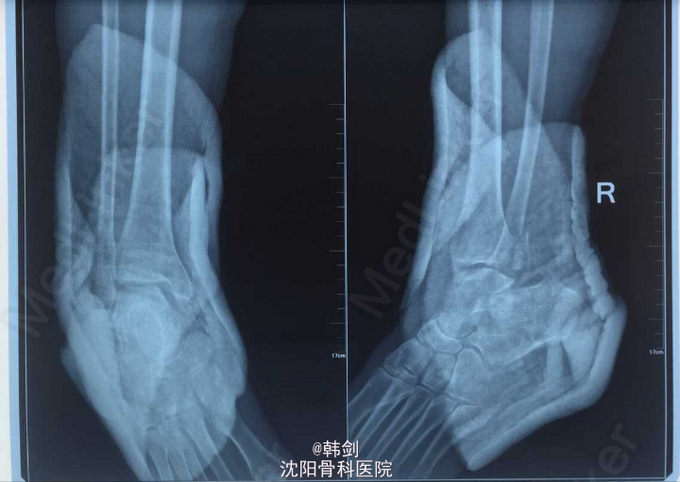

主诉:右踝外伤后肿痛、畸形、活动受限4小时. 病史:患者于2015年4月18日6:00,在家下楼时摔伤右踝,当即肿痛、畸形、活动受限,急来诊我院,经急诊拍片、阅片、查体后“右外踝骨折伴胫距关节脱位”为诊断收入院。病来无发烧,无头痛,头晕、头迷,无恶心、呕吐、无胸闷、气短等症,饮食 及二便正常.

查体:右踝皮肤完整无破溃,局部肿胀,畸形明显,可见皮下淤血,成青紫色,压痛阳性,可扪及骨擦音及骨擦感,异常活动存在,踝关节活动受限,末梢各趾活动自如,足背动脉搏动清。 辅查:WBC:6.91 10ˆ9/ L RBC:4.32 10ˆ12/L HGB:138g/L PLT:157 10ˆ9/ L ALT:24.0 U/L HBsAg:(-) 血型“O” RH(+) D-Dimmer:1.6 ug/ml 心电图:窦性心律,有束支传导阻滞,异常心电图。

初步诊断:右外踝骨折伴胫距关节脱位。 确定诊断:右外踝骨折伴胫距关节脱位。 补充诊断:右后踝骨折。 处理:1手法复位效果不佳 2患者入院后9天行手术治疗